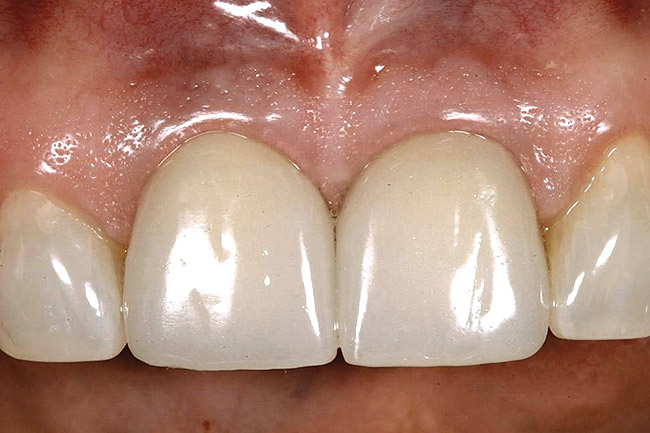

Figure 11  Soft-tissue levels were acceptable at the time of placement of the final restoration.

Figure 11